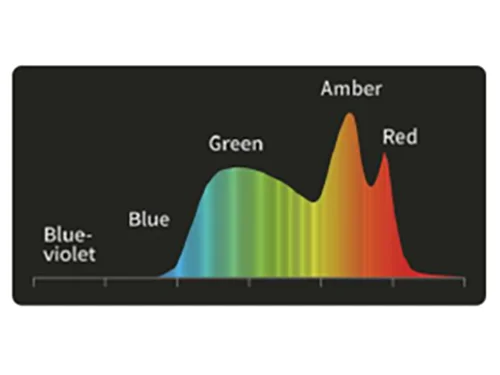

Технология многоспектрального композитного формирования изображения:

5 независимо управляемых высокоточных светодиодов обеспечивают работу специальных световых режимов для решения различных клинических задач в процессе диагностики и лечения.

Сочетание узкополосного красного, зеленого и желтого цветов улучшает видимость глубоких кровеносных сосудов и точек кровотечения за счет использования алгоритма слияния изображений и технологии автоматической обработки.

Слабая проницаемость и сильное рассеивание фиолетового и зеленого света позволяет хорошо визуализировать морфологию кровеносных сосудов слизистой оболочки . Кроме того, свет в этих двух диапазонах легче всего поглощается гемоглобином, что уменьшает отражение и рассеивание и повышает контрастность между кровеносными сосудами и окружающей тканью.

Оптимизация соотношения узкополосного фиолетового и красного цвета на основе белого цвета и использование алгоритмов сложения для повышения контрастности цветов изображения.